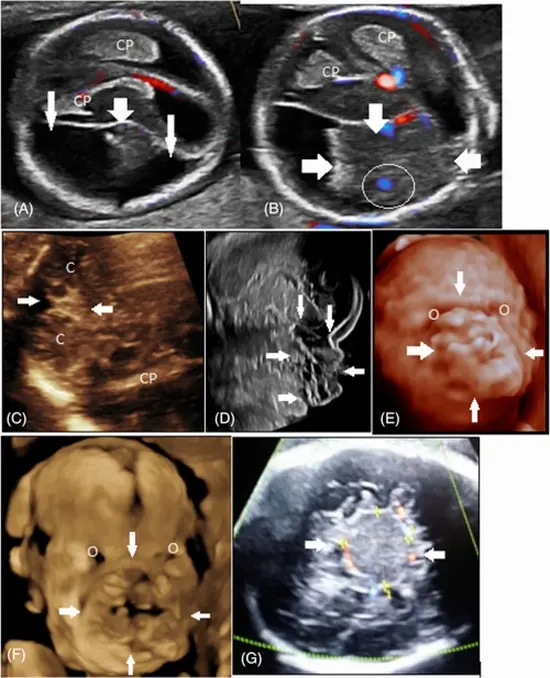

This pictorial essay focuses on ultrasound (US) and magnetic resonance imaging (MRI) features of fetal intracranial cysts. Intracranial cysts are common findings in prenatal imaging, and if great attention is paid to their size, location, and imaging features, they can be diagnosed accurately. They are usually detected by fetal ultrasound exams. However, when ultrasound data on cystic lesion characteristics is insufficient, MRI and fetal neurosonogram are the best options for detecting other associated anomalies. The prognosis is highly dependent on their location and whether they are associated with other fetal anomalies.